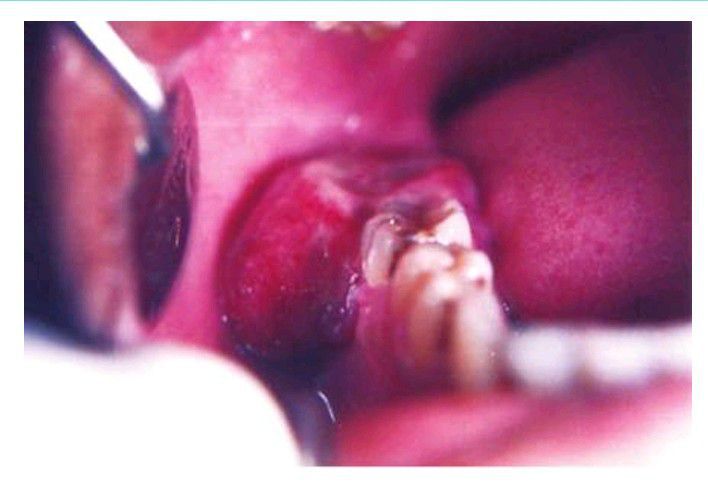

Peripheral giant cell granuloma

Peripheral giant cell granuloma showing ulcerated growth